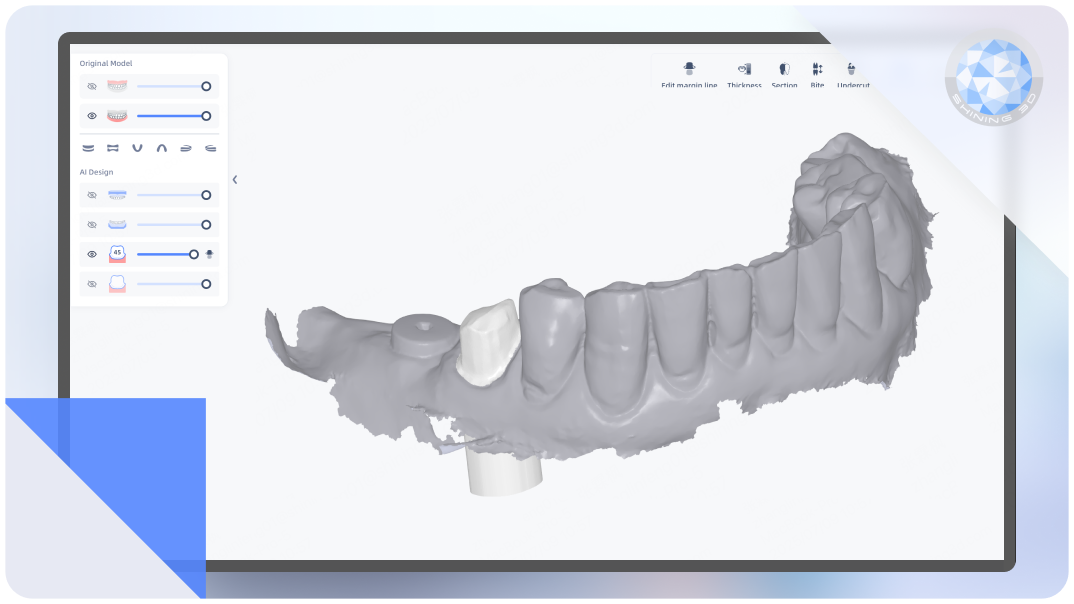

AI Crown

Intelligently generates dental crowns, auto-filling undercuts with meticulous precision.